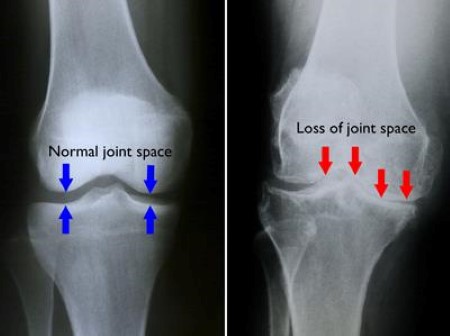

Bone on bone knees. If youre having problems with bone on bone knee pain I will tell you ways you can do to help ease the ache and probably not undergo surgery anymore here. The cartilage is here to prevent the bones from being damaged by rubbing together and causing pain and discomfort. Bone on Bone is reference to the increased severity of OA osteoarthritis in a joint.

Bone on bone is a common diagnosis when arthritisosteoarthritis has been present in a knee joint for years. Ad Clinically proven to increase your height naturally. Osteoarthritis is a condition in which the cartilage or cushioning on the end of bones deteriorates over time.

Cartilage comes in two types. Bone on bone knee pain is generally caused by excessive pressure on the joint due to the wearing away of cartilage. In the anatomy of a healthy knee between the bones you have a spongy tissue which is known as cartilage.

Eventually if the cartilage wears down completely bone will rub on bone. 482019 Bone on bone knee pain occurs when cartilage in the knee joint degenerates and the exposed bones rub against each other. This tissue of the knees is the natural shock absorber of the knee.